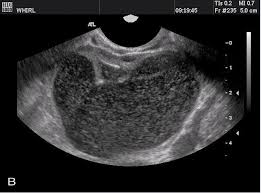

Two or three months ago, my jeans became tight around the waist, although i did not seem to gain any weight. But the two conditions are distinctly different. It can be mistaken for ovarian cancer or cysts. Sometimes cysts on an ultrasound can be mistaken for endometriosis, says dr. The link between endometriosis and ovarian cancer is well recognized and has perplexed physicians for a long time (3,4). Ovarian cysts are caused by multiple factors including the menstrual cycle, endometriosis, and benign tumors. Ovarian cancer is a tumor that forms on one or both of the glands that store eggs in the female reproductive system. There is evidence to suggest that endometriosis may slightly increase a woman's risk of developing this form of cancer. Women with adenomyosis are at higher risks of endometrial and thyroid cancers, while women with endometriosis are at higher risks of endometrial and ovarian cancers. Many women are told that they. On the other hand, ovarian cancer kills approximately 100,000 women every year worldwide. Also, endometriosis can cause cysts on the ovaries that may appear to be pelvic masses similar to ovarian cancer. However, endometriomas can sometimes pose an even greater diagnostic challenge, as they can be mistaken for functional ovarian cysts which grow each month as part of a woman's normal monthly ovulatory cycle.

I am 42 years old, and have been experiencing perimenopausal symptoms for about 4 years. The main difference is, while it can be a serious condition, endometriosis is not deadly or fatal. Many women are told that they. It is unclear what causes ovarian cancer, but risk factors include a family history of the condition and mutations in certain genes. Answer from tatnai burnett, m.d. Sometimes cysts on an ultrasound can be mistaken for endometriosis, says dr. These are the eight conditions that endometriosis is often mistaken for. Eaoc is described as an ovarian cancer having both cancer cells and endometriosis in the same ovary, presence of cancer in one ovary, and endometriosis in second ovary or presence of ovarian cancer and pelvic endometriosis. It can be mistaken for ovarian cancer or cysts. Like with bladder infections, endometriosis can cause painful urination, so these symptoms can. Some studies suggest that endometriosis increases that risk, but it's still relatively low. And there's no genetic trait associated with endometriosis that could lead to cancer. Ovarian cysts are caused by multiple factors including the menstrual cycle, endometriosis, and benign tumors.

One to two months ago,i noticed that i seemed more aware. It can be mistaken for ovarian cancer or cysts. Sometimes cysts on an ultrasound can be mistaken for endometriosis, says dr. The pelvis also reacts to hormonal restoration and progesterone deficiency antibiotics as it affects over 5. Each year, according to the centers for disease control and prevention (cdc). Can ovarian cancer be mistaken for endometriosis? Many women are told that they. The link between endometriosis and ovarian cancer is well recognized and has perplexed physicians for a long time (3,4). The main difference is, while it can be a serious condition, endometriosis is not deadly or fatal. Many other symptoms can have similar symptoms such as endometriosis, fibroids uterine myomas, gastrointestinal conditions such as colitis, ibs, diverticulosis and benign ovarian cysts. what makes the situation more vexing is if the patient has only a few symptoms. How do you treat endometriosis? Plus i am still in pain and i have to wait two weeks for my procedure. I am 42 years old, and have been experiencing perimenopausal symptoms for about 4 years.